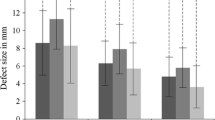

At the follow-up assessment, the post-operative OLT was assessed using CTA. The thickness of the repaired tissue was compared with the thickness of adjacent normal talar dome cartilage and classified into the following four grades: (0) no growth; (1) growth less than 50% of the adjacent normal cartilage thickness; (2) more than 50% of the adjacent normal cartilage thickness; and (3) similar to the thickness of adjacent normal talar dome cartilage (Table 1) [21, 32].

The proportion of repaired tissue of OLT with grade 3 increased over time (Table 2). At the final follow-up of each ankle, tissue growth of grades 1, 2, and 3 was observed in 10, 9, and 21 ankles, respectively. As a result, defect filling was observed in 40 ankles (95.2%).

Tissue growth and subchondral bony consolidation increased over time in most cases (Figs. 1, 2). Hypertrophic tissue and poor tissue growth were also observed. Uncontained shoulder lesions either restored the previous shape of the talus with cartilaginous signal or showed in situ tissue growth (Fig. 3). One lesion even achieved congruency of the joint by forming tissue growth at the confronting plafond surface (Fig. 3c). These lesions were classified as given in Table 3. A debrided OLT before microfracture is shown in Fig. 4.

The ROIs and tissue growth were significantly improved at the 1-year follow-up compared with those at six months (p = 0.001 and 0.007, respectively); however, the overall size of the subchondral cystic lesions did not decrease [not significant (n.s.)].